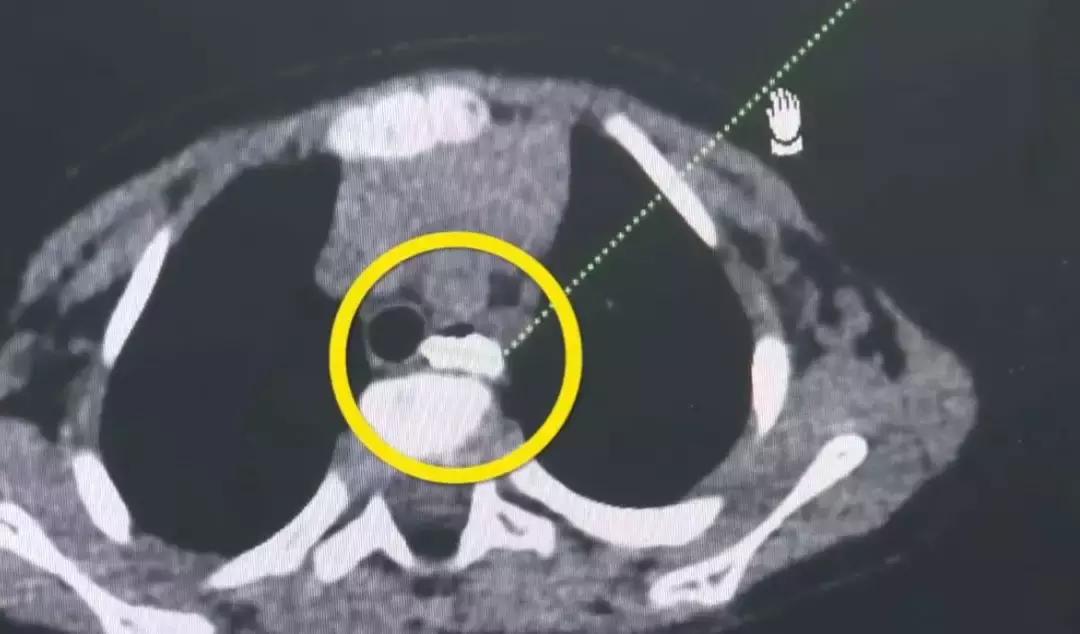

据深圳市儿童医院耳鼻喉科医生潘医生介绍,男童吞下玻璃后的症状是老流口水,吃东西受影响,只可以喝水,不能吃固体的食物,没有呼吸困难但有吞咽困难,其他的生命体征都比较稳定,做CT检查时发现这块玻璃在食管第二狭窄的地方,外面就是心脏和主动脉弓的位置,处于比较危险的地方,玻璃距离主动脉弓只有3~5毫米。

医生说手术的风险主要在于取这块玻璃,取的过程可能会刺破大血管,引起大出血,因为玻璃比较光滑不好夹,总共取了三次,换了三个钳子才取出来。目前,男童已无大碍。